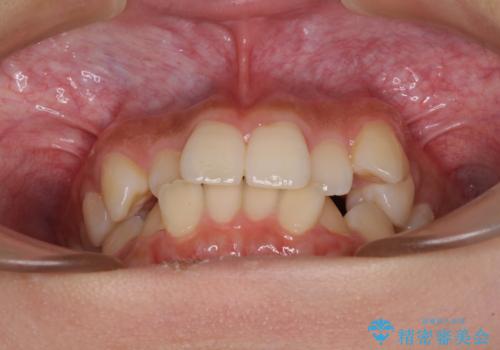

- 上下前歯のデコボコと八重歯を気にして来院された患者様です。

叢生を解消する際に出っ歯とならないようにするために、上下左右の小臼歯計4本を抜歯することとしました。